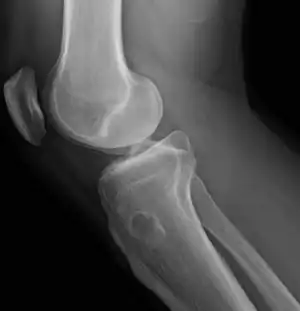

Osteochondroma, a common type of non-cancerous chondrogenic tumors

Osteochondroma[2]

Chondroblastoma[2]